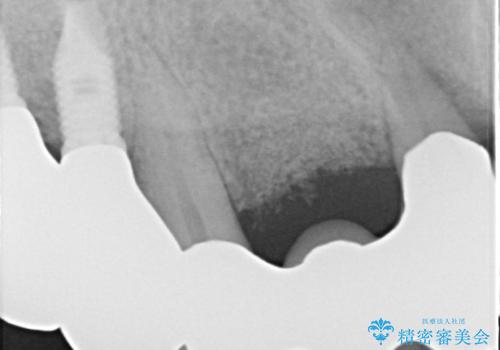

歯周病におかされた前歯の再建治療

- 歯周病により欠損が生じた歯槽骨、まずは再生治療をおこなう

→治癒後、確定外科を行い完全に歯周ポケットを除去し、最終的に歯周補綴をおこなう

歯周病が進行してしまうと、歯周外科による処置が不可欠になります。

様々なリスクがありますが、唯一歯周病を除去することが可能な手段です。